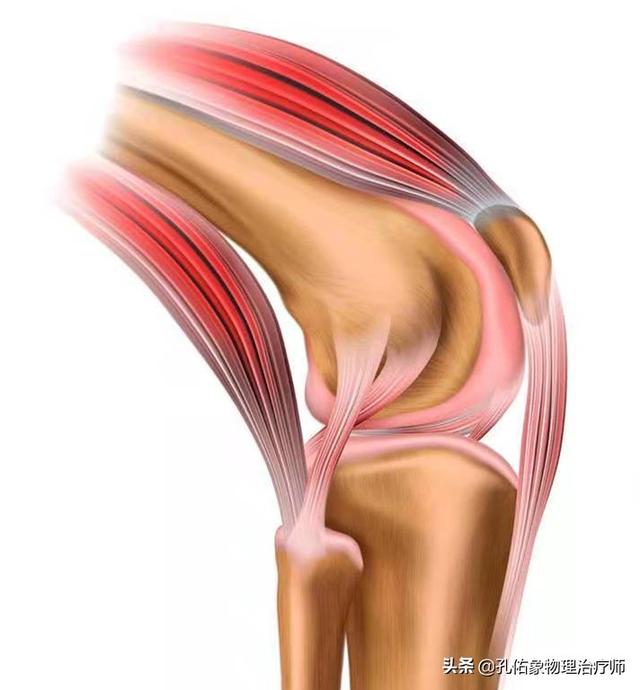

In unserem Kniegelenk gibt es zwei Menisken auf der medialen und lateralen Seite, der mediale Meniskus ist mit dem medialen Seitenband und der medialen Gelenkkapsel verbunden, während der laterale Meniskus mit der lateralen Gelenkkapsel verbunden ist, und der Quadrizeps, der Semimembranosus-Muskel und der Popliteus-Muskel auf der Rückseite sind ebenfalls mit dem Meniskus verbunden. Der Meniskus ist eine sehr wichtige Struktur in unserem Körper, die nicht nur die Tiefe der Gelenkgrube vergrößert, die Verbindung zwischen Oberschenkel- und Wadenbeinknochen anpassungsfähiger macht und die Stabilität des Kniegelenks erhöht, sondern gleichzeitig auch das Kniegelenk schützt und als Stoßdämpfer fungiert.

Im täglichen Leben ist jedoch dieDer Meniskus wird oft übersehen, aber Knieschmerzen hängen auf die eine oder andere Weise mit ihm zusammen!. Um ihn besser kennen zu lernen, ist es auch notwendig, die Nährstoffversorgung des Meniskus zu kennen:

Der Meniskus stützt sich stark aufBlut和Synovialflüssigkeit in der Gelenkkapsel (Medizin)Der Meniskus wird im Wesentlichen von zwei Substanzen versorgt: Das äußere 1/3 des Meniskus ist durchblutet und hat einen kleinen Anteil in der Mitte, während das innere 1/3 nicht durchblutet ist und hauptsächlich von der Synovialflüssigkeit der Gelenkkapsel ernährt wird.

Wenn der Meniskus degeneriert ist, kann der Meniskus beschädigt werden, wenn Sie unbeabsichtigt in die Hocke gehen oder aufstehen und Ihren Körper verdrehen. Offensichtlich tragen Probleme mit der Blutversorgung, der Dämpfung und der Synovialflüssigkeit direkt zu Kälte, Schmerzen und Rasseln bei, die Sie bei Bewegungen verspüren.

Die Krankheit ist nicht nur ein Problem der Knochen und Gelenke und des Gelenkknorpels, sondern auch der Sehnen, Bänder und Kniescheiben um das Kniegelenk herum, die durch Belastung und Entzündung gereizt werden und Schmerzen und Unbehagen verursachen.

Kälte und Schmerzen im Knie deuten auf eine Entzündung und schlechte Durchblutung des Kniegelenks hin. Beachten Sie, dass es sich hier um eine aseptische Entzündung handelt, d. h. es liegt keine bakterielle oder virale Infektion vor, und das Knie ist nicht rot, geschwollen oder fiebrig. Die Entzündung tritt am ehesten an drei Stellen auf: dem infrapatellaren Fettpolster (unterhalb der Kniescheibe), dem medialen Seitenband und dem Schleimbeutel. Die Ursachen für die Entzündung sind vor allem Kältereiz, Überanstrengung, Fettleibigkeit und Traumata.